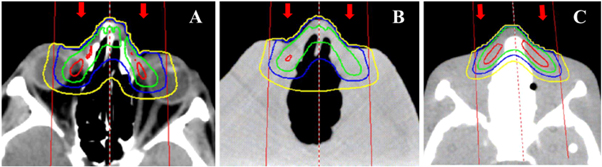

Recall that we suppressed differences in observed differences in dose distributions between the printed personalized phantom and the patient by manually reassigning or overriding tissue densities in the CT images of the patient and phantoms. This was beneficial in it suppressed a source of experimental bias and it also facilitated a more direct comparison of results. However, to improve pass rates, a better long-term approach would be to develop printing capabilities that allowed continuous and calibrated modulation of mass density, a wider dynamic range of mass density (especially high densities needed for bone), and to print with multiple materials (e.g. soft tissue and bone substitute plastics). That said, the present results revealed that, even with the current limitations on printing capabilities, the superior performance of the printed personalized phantom over the molded reference phantom was still evident. In fact, this superiority underscores the importance to accurately model surface geometry (e.g. the amputated nose) and pronounced internal heterogeneities (e.g. the nasal sinus and paranasal sinus cavities and their interfaces) (figure 7).

Figure 7. Transverse images of the dose distributions from 6 MeV electron beam in (A) the patient, (B) the printed phantom, and (C) the reference phantom. The red, blue, green, and yellow isodose lines correspond to 80%, 60%, 40%, and 20% of the maximum dose. The beam placement is shown by the red lines and the beam direction is indicated by the red arrows.

Download figure: